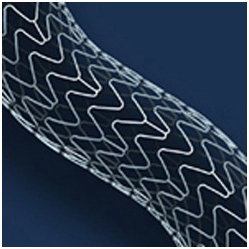

2. Отягощающим фактором является ИБС со стенозированием коронарных артерий, обнаруженным по данным МСКТ коронарных артерий. С учетом того, что при проведении Холтеровского мониторирования ЭКГ имеется стресс-индуцированная ишемия миокарда, то в ближайшее время показано проведение селективной коронарной ангиографии. При необходимости будут установлены стенты без лекарственного покрытия с последующей антикоагулянтной терапией гепарином и отменой данного препарата в минимальные сроки перед очередным оперативным вмешательством. Выбор данного вида стентов обусловлен возможностью проведения менее интенсивного режима антиагрегантной терапии в условиях предстоящей операции нефрэктомии, а также в послеоперационном периоде.

18.08.2011 интервенционным кардиохирургом в область стеноза проксимальной трети передней межжелудочковой артерии проведен баллонный катетер со стентом «Мульти-линк 8» размерами 3×12 мм, произведена имплантация.

В дистальную часть правой коронарной артерии проведен проводник 0,014". В область стеноза проведен баллонный катетер со стентом «Мульти-линк 8» размерами 3×12 мм, произведена имплантация.

На контрольных ангиограммах получен хороший кровоток

Ишемическая болезнь сердца. Стенокардия напряжения II функционального класса. Атеросклероз коронарных артерий. Ангиопластика и стентирование передней нисходящей артерии стентом без лекарственного покрытия «Мульти-линк 8» размерами 3×12 мм. Ангиопластика и стентирование правой коронарной артерии стентом без лекарственного покрытия «Мульти-линк 8» размерами 3×12 мм от 18.08.2011.